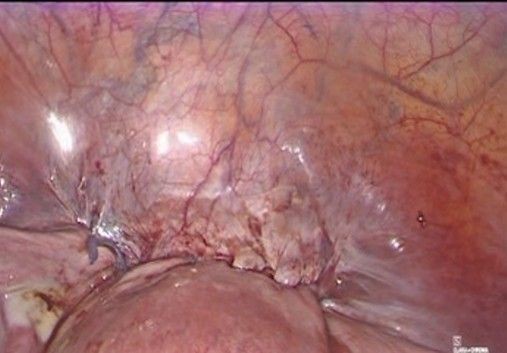

- Final review and closure (Figure 12-13): The absence of bleeding is verified along the dissection path and around uterine vessels, the vesicouterine peritoneum is repositioned over the dissected area, covering the tape knot, and trocars are removed under direct vision and the cavity is deflated.

Figure 12: Repositioning of the vesicouterine peritoneum